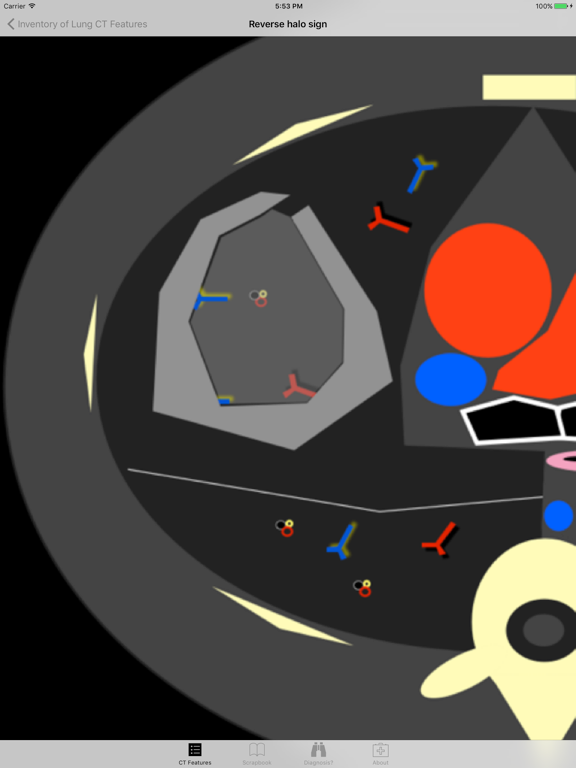

Introducing the Lung CT Field Guide app, an excellent resource for a wide-range of physician specialists, in particular radiologists and pulmonologists. One of the critical steps in interpreting a lung CT is identifying and appropriately describing imaging findings in the lung. Review and explore lung CT images and color graphic illustrations of the fundamental patterns of lung disease on CT. Play with an experimental diagnosis engine that will try to suggest a differential diagnosis list to consider with any number and combination of lung CT findings! Includes over 100 carefully curated CT images and color graphic illustrations.

· Nearly 60 color graphic illustrations of prototypical lung CT imaging features